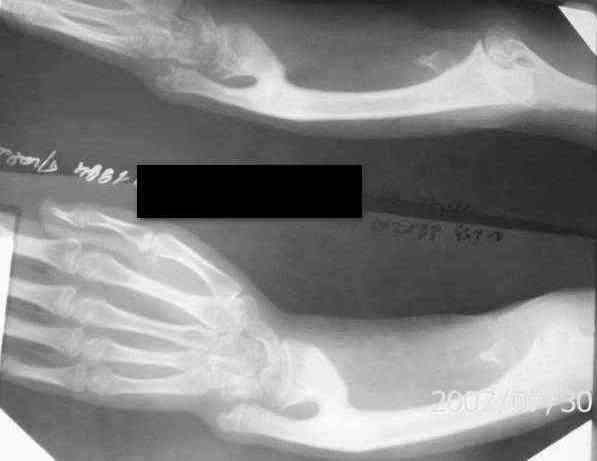

Лучевая косорукость у девочки 12 ти лет |

Здравствуйте, уважаемые коллеги. К нам обратилась девочка 12 ти лет с жалобами на деформацию левого предплечья. Девочка перенесла сепсис ,остеомиелит лучевой кости в возрасте 4х лет. Клинически выражена лучевая косорукостью, просупинационные движения отсутствуют, сгибание в локтевом суставе в полном объеме. Посоветуйте, пожалуйста тактику лечения.Спасибо за Ваше внимание. Игорь

Огромное спасибо ,за Ваше внимание .Функция кисти удовлетворительная, просупинационные движения отсутствуют. Неврологических и трофических нарушений не обнаружено.

По нашему мнению необходима коррекция деформации АВФ.( выполнить остеотомию лучевой кости у основания синостоза и проводить удлинение ,вторым этапомвыполнить коррегирующую остеотомию лучевой . С уважением, Игорь